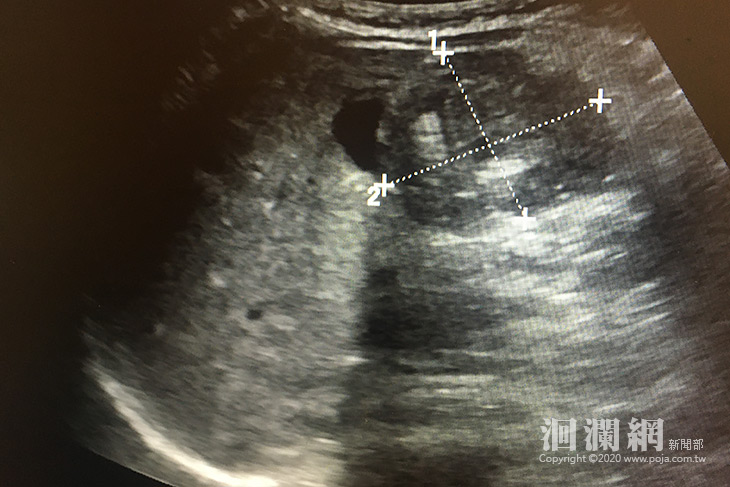

日前一歲三個月張姓男童突然出現一陣一陣哭鬧的情形,安撫後可稍微睡著,但是過一陣子醒來又開始哭,間隔的時間越來越短,母親焦急赴花蓮慈濟醫院急診求診。小兒腸胃科張雲傑醫師立即做腹部超音波檢查,發現「腸套疊」後立即以超音波搭配生理食鹽水灌腸,做腸套疊復位術。